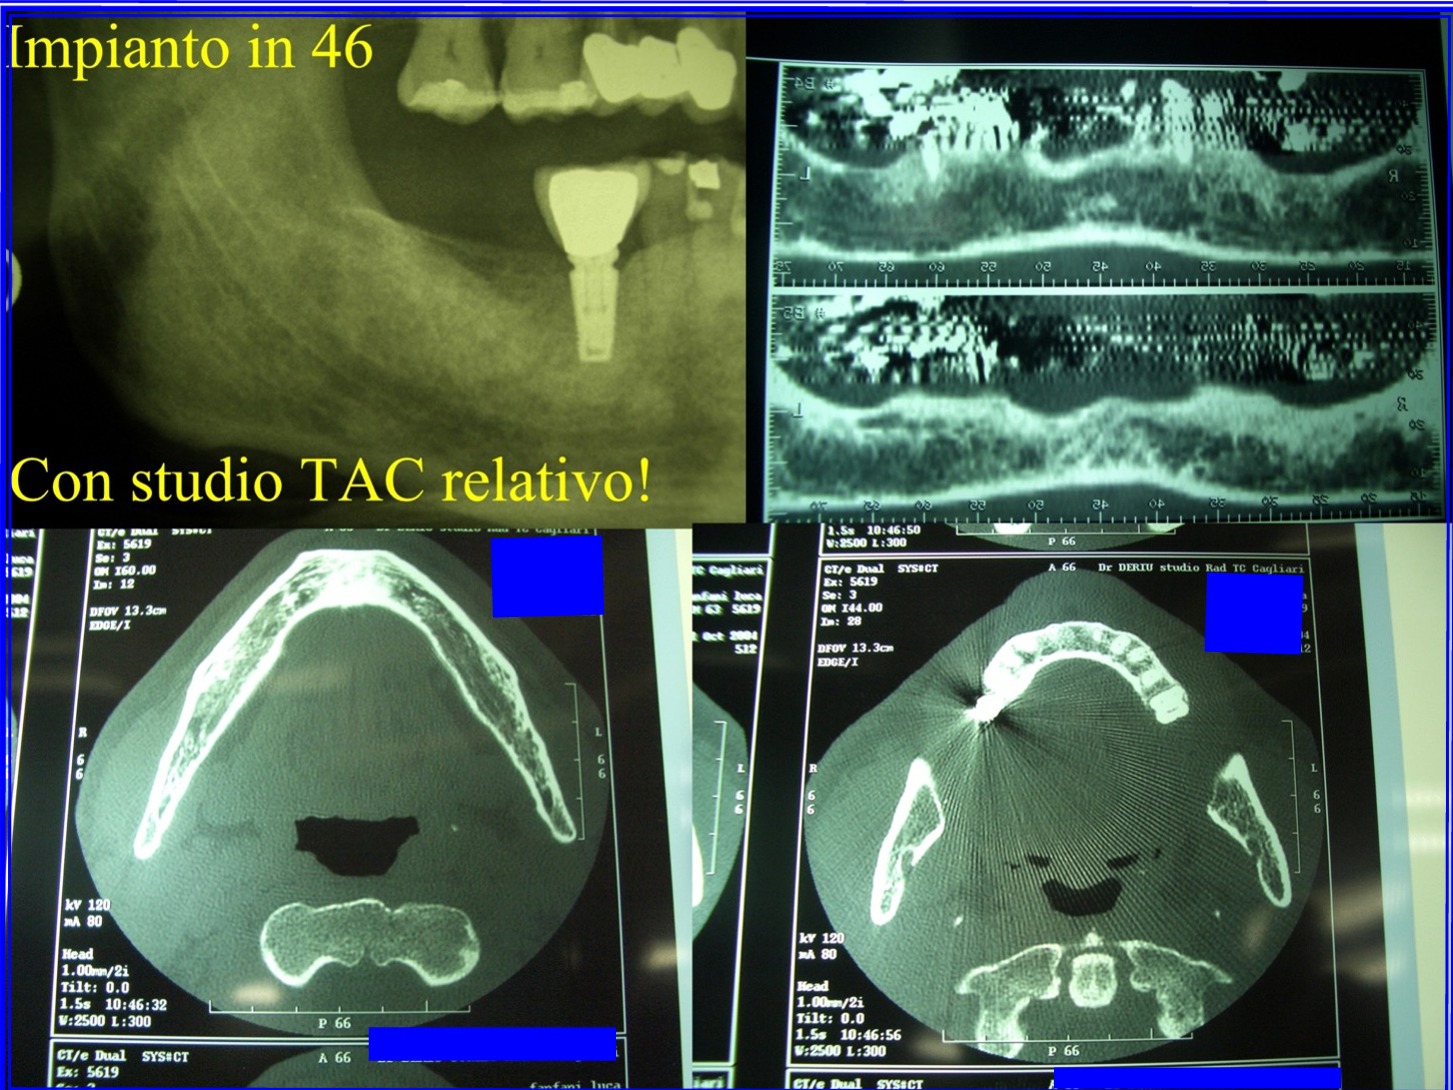

Ieri mi sono stati inseriti 2 impianti ma quello per la sostituzione del molare superiore alla radiografia sembra molto inclinato e vicino al secondo molare. In questa situazione ho paura che la corona che verrà applicata possa essere non simmetrica con differenza di carico sbilanciato. Questo alla lunga non potrebbe creare danni all'impianto o all'osso? Il medico afferma che va bene e che si tratta della normale prospettiva radiografica. Ma a vedere l'impianto al molare inferiore eseguito 10 anni fa presso un'altro medico quest'ultimo sembra perfettamente centrato. Potreste darmi per cortesia un vostro parere? Grazie, Cordiali Saluti

Gentile Sig. Angelo, l'impianto non è molto inclinato ed è leggermente più vicino al molare che al premolare. Comunque le distanze minime sembrano rispettate e non vedo come ci possano essere dei problemi nell'eseguire la fase protesica e possibili danni all'impianto o all'osso. Cordiali saluti

Egregio paziente, il mio parere è che va bene così. Si fidi del suo dentista che ha operato in un contesto biologico e con massima attenzione (ha brillantemente inserito un impianto in pos 35 evitando l'alveolare inferiore). Ciò che appare da una OPT è il risultato bidimensionale del nostro lavoro: se l'operatore decide di inserire un impianto in un determinato sito, è evidente che ha scelto il sito migliore avendo una visione tridimensionale e reale della zona. Cordialmente.